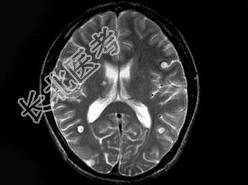

- 单项选择题男,29岁, 头痛不适半个月,MRI扫描如图, 最可能的诊断是 ( )

A、脑转移瘤

B、脑囊虫病

C、脑弓形虫病

D、脑脓肿

E、未见异常